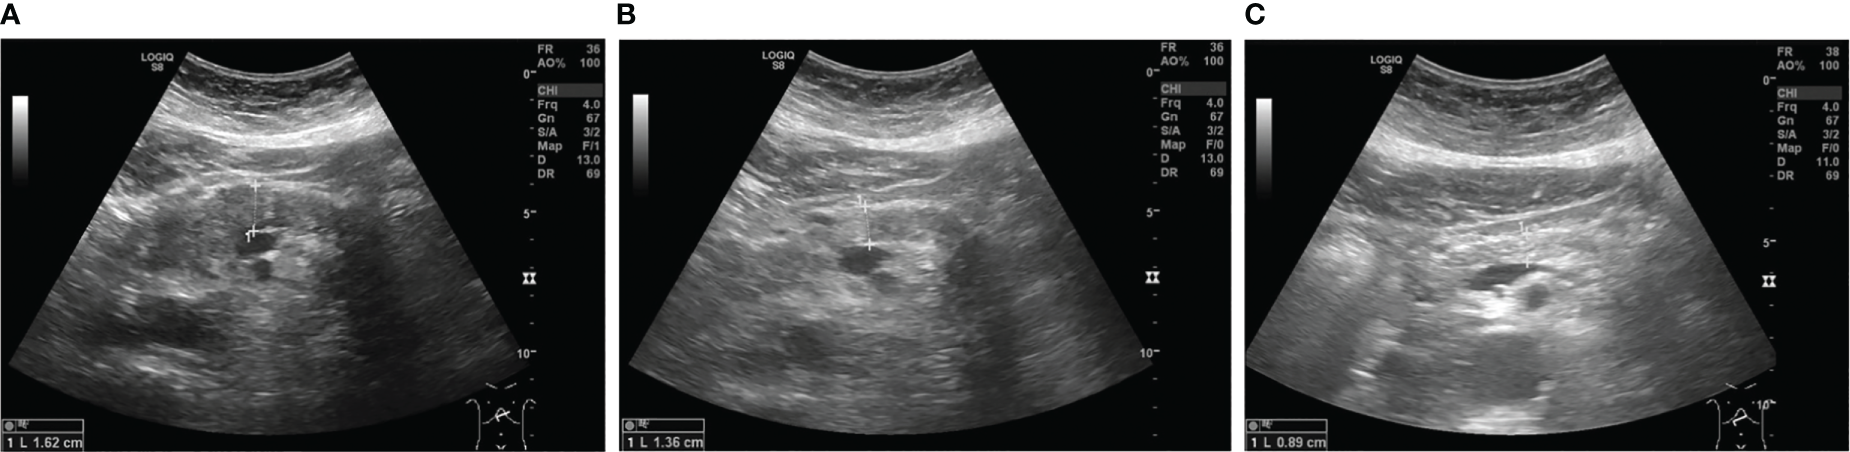

Within the follow-up period of one year there has been no relapse of symptoms. Anti-diabetic therapy could be de-escalated to a combination therapy with metformin and empagliflozin without insulin. Follow-up sonography was unremarkable for signs of inflammation as seen upon initial presentation (Figure 3).

Figure 3

Sonographic images of the pancreatic body showing diffuse hypoechoic swelling upon admission (A), which decreased under steroid treatment (B) and 11 months after the first dose of vedolizumab (C).